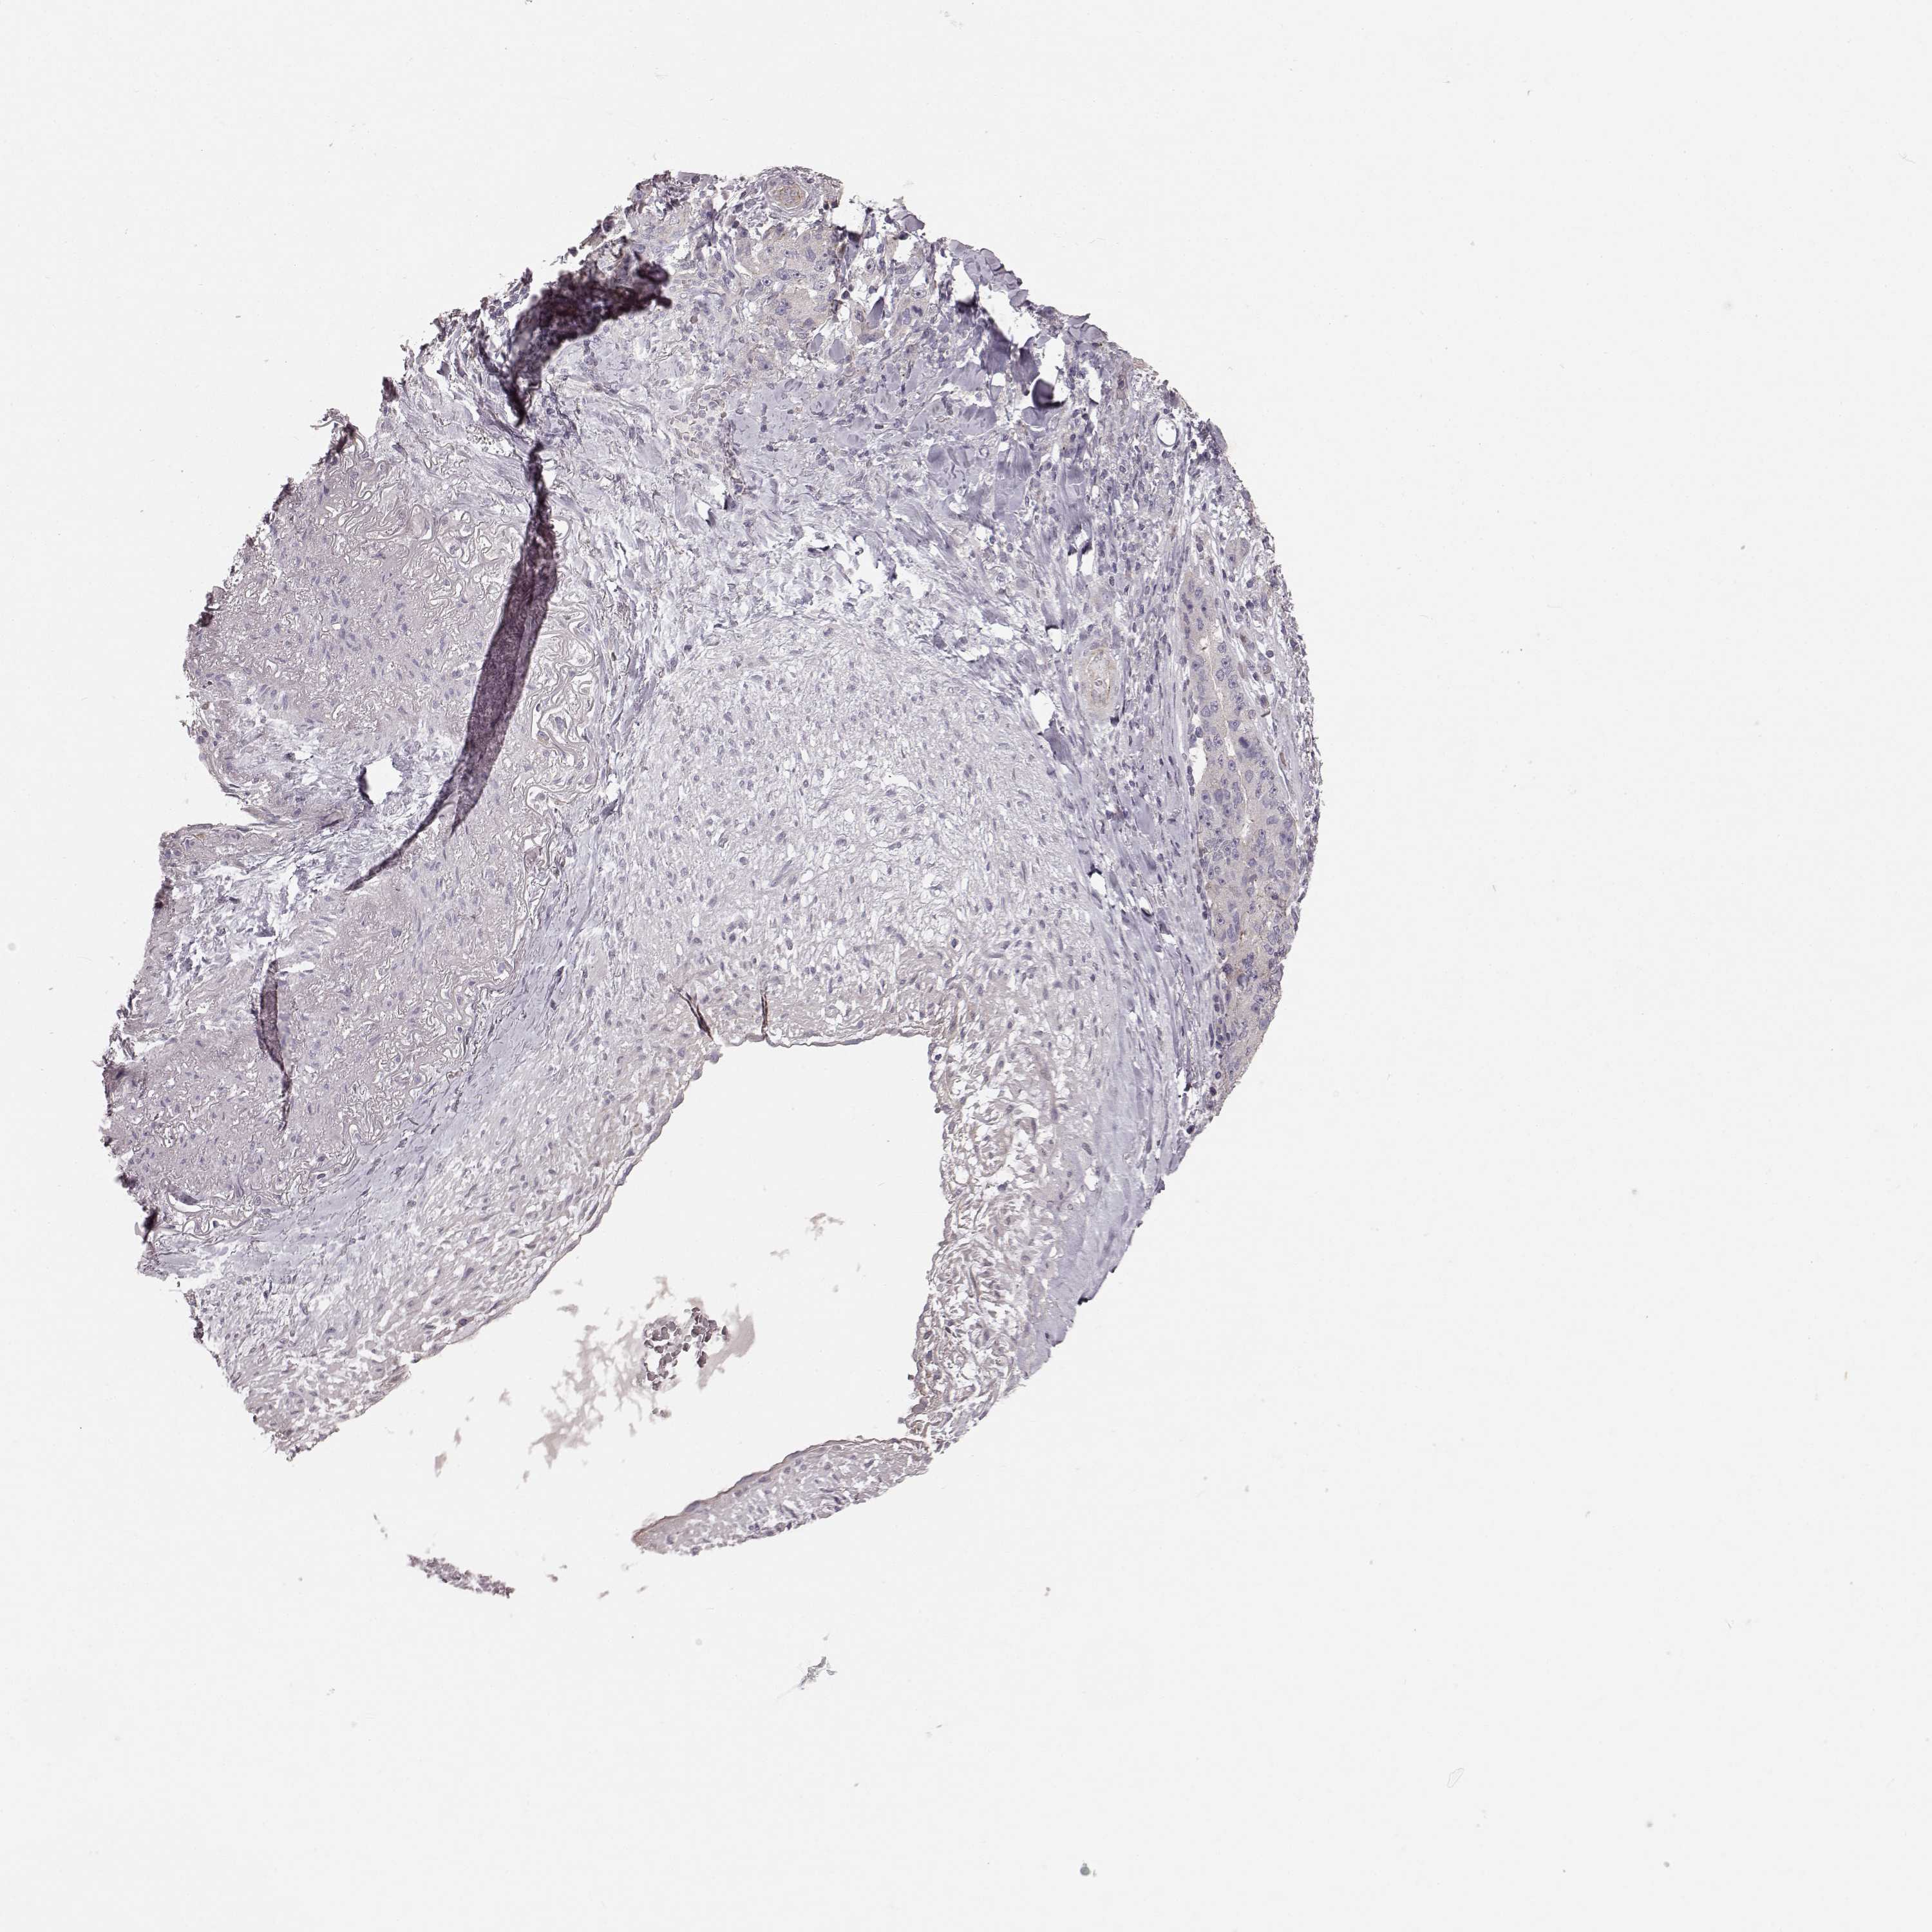

LUNG ADENOCARCINOMA (TCGA) - Interactive survival scatter ploti

The Survival Scatter plot shows the clinical status (i.e. dead or alive) for all individuals in the patient cohort, based on the same data that underlies the corresponding Kaplan-Meier plots. Patients that are alive at last time for follow-up are shown in blue and patients who have died during the study are shown in red.

The x-axis shows the expression levels (FPKM) of the investigated gene in the tumor tissue at the time of diagnosis. The y-axis shows the follow-up time after diagnosis (years). Both axes are complimented with kernel density curves demonstrating the data density over the axes. The top density plot shows the expression levels (FPKM) distribution among dead (red) and alive patients (blue). The right density plot shows the data density of the survived years of dead patients with high and low expression levels respectively, stratified using the cutoff indicated by the vertical dashed line through the Survival Scatter plot. This cutoff is automatically defined based on the FPKM cutoff that minimizes the p-score. The cutoff can be changed by dragging the vertical line or by entering a cutoff value in the square labeled "Current cut-off".

Under the Survival Scatter plot the p-score landscape (black curve; left axis) is shown together with dead median separation (red curve; right axis). Dead median separation is the difference in median mRNA expression between patients who have died with high and low expression, respectively. It is calculated as follows: median FPKM expression of dead patients with high expression - median FPKM expression of dead patients with low expression. This is intended to aid the user in visually exploring custom cutoffs and the associated p-scores and dead median separation.

Individual patient data is displayed and can be filtered by clicking on one or more of the category buttons on the top of the page. Categories describing expression level and patient information include: high, low, alive, dead, female, male and tumor stages. The scale of the x-axis can be toggled between linear and log-scale by clicking on the "x log" button. Mouse-over function shows TCGA ID, patient information and mRNA expression (FPKM) for each patient.

& Survival analysisi

Kaplan-Meier plots summarize results from analysis of correlation between mRNA expression level and patient survival. Patients were divided based on level of expression into one of the two groups "low" (under cut off) or "high" (over cut off). X-axis shows time for survival (years) and y-axis shows the probability of survival, where 1.0 corresponds to 100 percent.

SLC22A18 is not prognostic in Lung Adenocarcinoma (TCGA)

: 6.26

Average pTPM 15.6

Number of samples 497